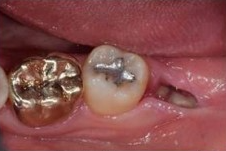

✅3일차 / 4일차

4일차에 실밥이 제거된 모습입니다.

보통은 발치후 일주일 정도 후

내원하여 실밥제거와 함께

회복상태를 체크합니다.

4~5일차가 되면

봉합실이 느슨하다고 느껴질 수 있는데

이는 잇몸이 어느정도 아물고

안정화가 되어 그런것입니다.

모르는 사이 풀렸다해도

큰 걱정은 하지 안하도 되며

약속한 날짜에 치과에 방문하여

실밥을 제거하고 소독을 받으면 됩니다.

실밥제거시 잇몸을 스치는 느낌이 있지만

별다른 통증은 거의 없는 수준입니다.

3일차 / 4일차